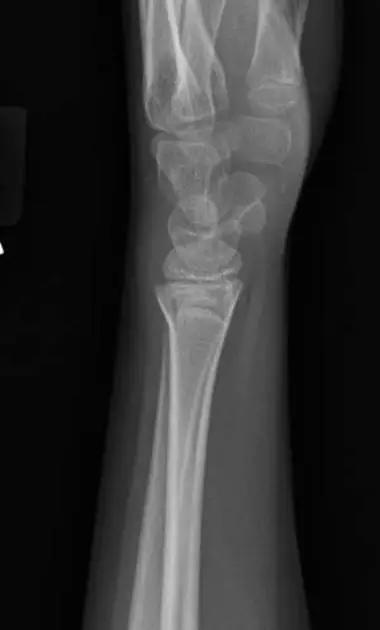

2. Colles 骨折

桡骨远端骨折,伴有桡骨远端向背侧的移位,可以有或没有尺骨干的骨折。具有这几个特征:背侧粉碎、向背侧成角、向背侧移位且挠骨短缩的关节外骨折。

典型 colles 骨折,枪刺样、餐叉样畸形